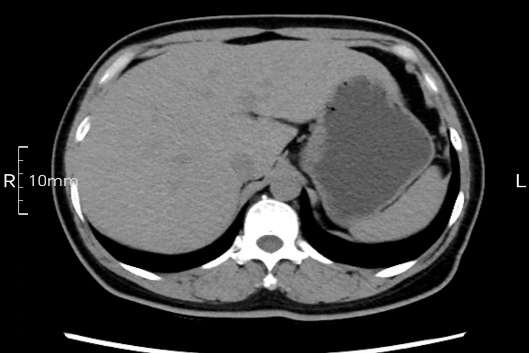

看看下面三幅便知遵醫囑的重要性。

沒禁食,胃內全是食物,導致胃壁顯示不清。